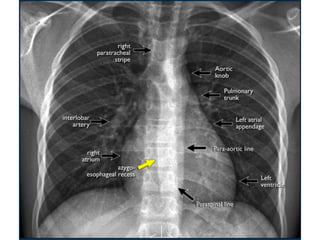

Mediastinal lines/stripes

Azygo-esophageal line/recess

• The azygo-esophageal recess is the region

inferior to the level of the azygos vein arch in

which the right lung forms an interface with

the mediastinum between the heart anteriorly

and vertebral column posteriorly.

It is bordered on the left side by the

esophagus.

• Widening of the paratracheal line (> 2-3mm)

may be due to lymphadenopathy, pleural

thickening, hemorrhage or fluid overload and

heart failure.

• Displacement of the para-aortic line can be

due to elongation of the aorta, aneurysm,

dissection and rupture.